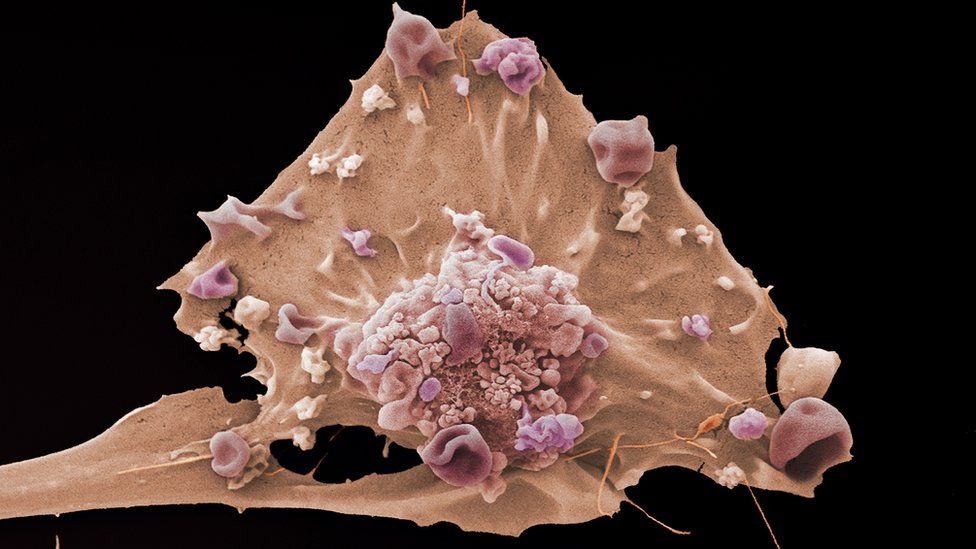

Naučnici koji rade na istraživanju raka u Velikoj Britaniji i Sjedinjenim Američkim Državama udružili su snage kako bi proučavali oboljenja od raka.